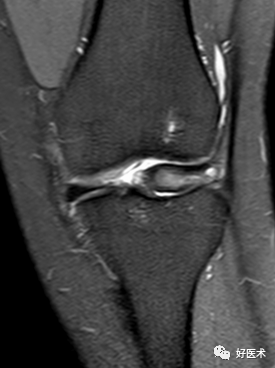

5)Segond骨折:

胫骨平台前外侧撕脱骨折(胫骨平台腓骨尖上方,关节线下方的撕脱骨折),多因为下肢过度内翻加内旋暴力所致。

骨折本身无特殊治疗,但其强烈提示ACL损伤(75–100%)。